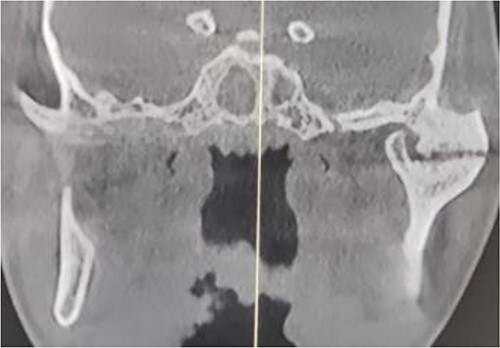

Figure 3.

Preoperative computed tomography (coronal section): left-sided TMJA with radiographic suggestion of previous condylectomy at right-sided temporomandibular joint.